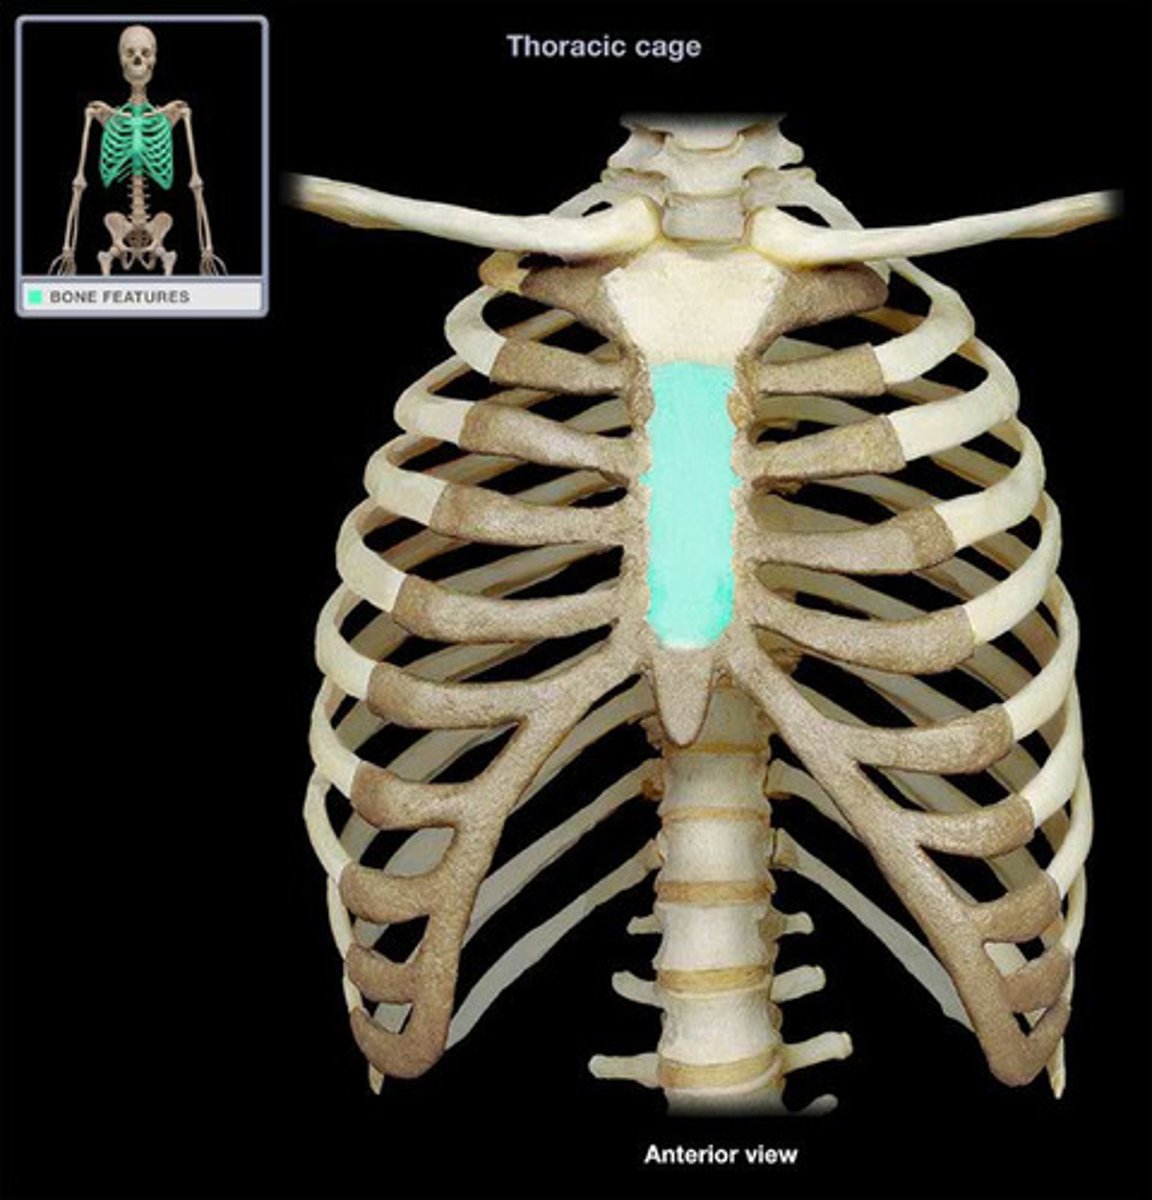

Sternum

Body